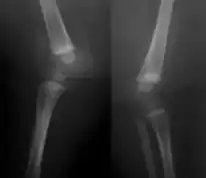

X-ray knees